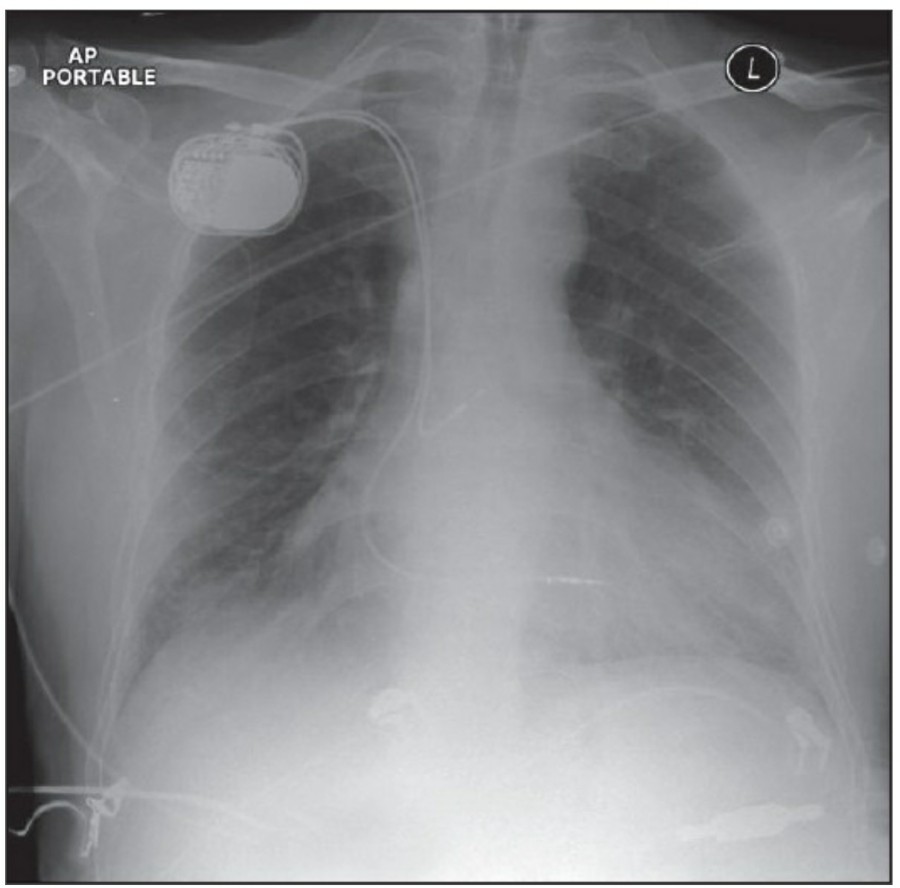

Cardiac pacing devices

Temporary cardiac pacemaker는 cephalic vein이나 subclavian vien을 통해 right ventricl에 거치시킨다. AP, lateral chest X ray가 위치 확인을 위해 필요한다. Cardiac pacemaker의 tip은 심첨부에 위치해야 하며, pacemaker wire의 line이 꺾여 있어서는 안 된다. Lateral radiograph가 cardiac trabeculae 안에 묻혀 있는 tip을 확인하는데 도움이 된다. 제대로 거치된 게 맞다면 그 tip은 epicardial fat pad의 3, 4mm 안에 있어야 하며, 그 이상 넘어간다면 myocardium 천공 가능성이 있다. Coronary sinus 안에 들어갔을 경우 lateral radiograph 상에서 posterior 쪽에서 발견할 수 있다.